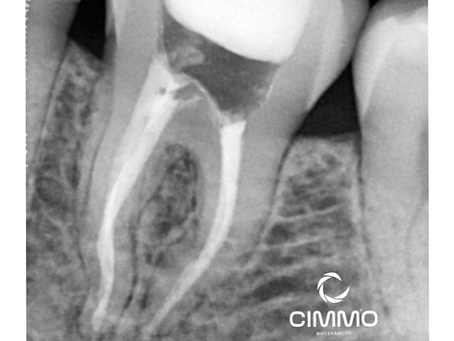

Casos clínicos

Explore nossos casos clínicos sobre o uso de cimento biocerâmico Cimmo: aplicações reais, abordagens práticas e resultados transformadores para inspirar e aprimorar sua prática odontológica.